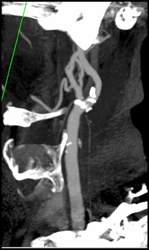

Carotid Stenosis